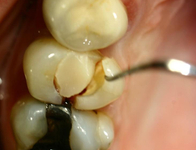

O atrito relacionado ao bruxismo que atinge a dentina pode resultar em dor e hipersensibilidade dentária

Da coleção do Dr. Alessandro Bracci